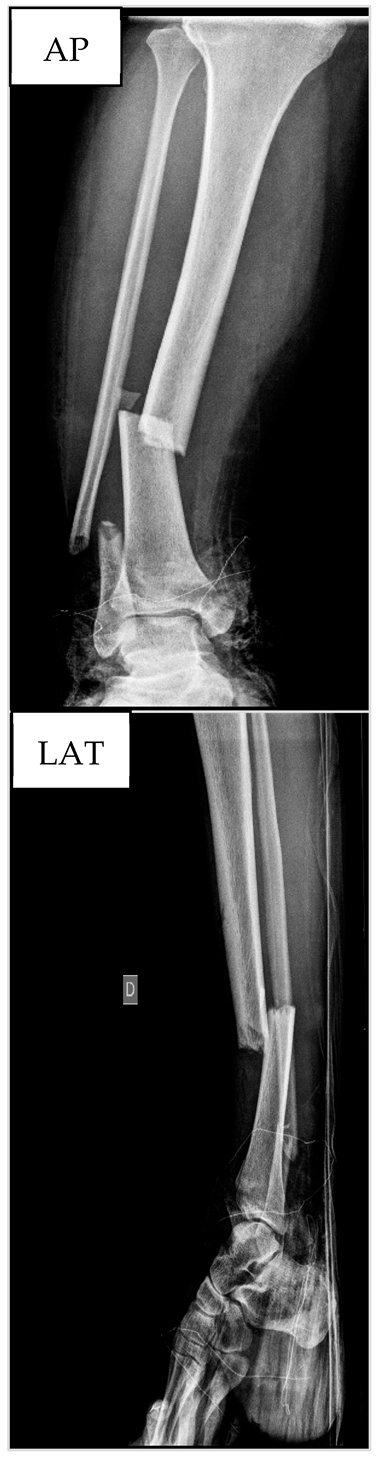

3.4. Patient nº4